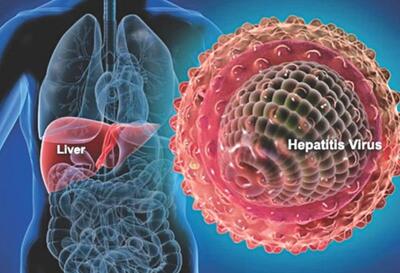

راه نفوذ ویروس هپاتیت C به سلولها کشف شد

دانشمندان چگونگی نفوذ ویروس هپاتیت C به سلولها را کشف کردهاند.این یافته جدید امکان تولید واکسن برای این بیماری مرگبار